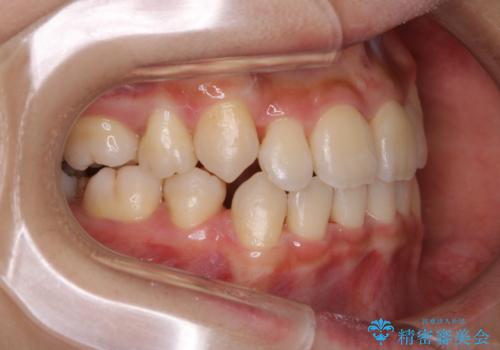

PMTC60分コースを行いました。紅茶による着色が全体的に付着していました。

インビザライン中の患者様で、紅茶を飲んだ後にそのままマウスピースをはめていたそうです。着色が、かなり目立っていた為、追加アライナーのタイミングで全体の着色を除去し、とても綺麗になりました。